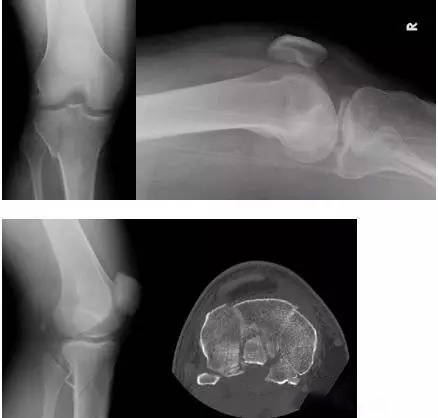

(10)Bumper 骨折(保险杆骨折)

是汽车保险杠撞击膝关节外侧,导致的胫骨平台粉碎性骨折,伴有软骨面挫裂和腓骨头骨折。初诊,X 线上正侧位很容易忽略平台的粉碎性,CT 平扫及重建可明确伤情,MRI 可了解副韧带及叉韧带情况。